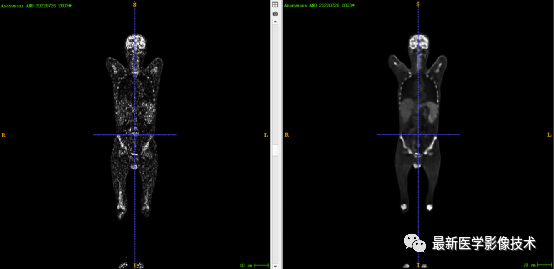

7.5、低剂量50重建结果

第一张是低剂量50的PET图像,第二张是full剂量PET图像,第三张是网络重建的PET图像。